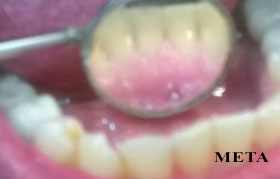

σοδοβολή